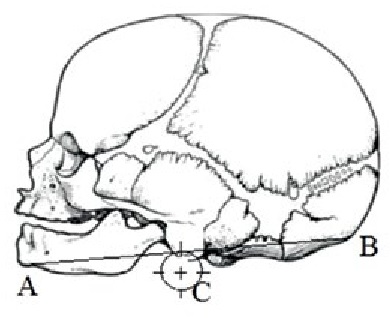

Results. During the mid-gestation period, with the growth of the fetus, the auricle normally shifts upward relative to the mandible. At the beginning of the study period, the auricle is located just below the angle of the lower jaw. Its central part (C) is below the line (AB) connecting the gnathion point and the external occipital protuberance. The perpendicular from the conditional center of the auricle to the line AB is half the diameter of the auricle 3.7 ± 1.1 mm. In the second age group, the auricle is located at the level of the branch and angle of the lower jaw Its conditional center (C) is below the line AB and is ¼ of the diameter of the auricle 3.1 ± 0.8 mm. By the end of the mid-gestation period, the auricle is displaced to the level of the processes of the lower jaw above the notch. Its central part is above line AB, the perpendicular from point C to line AB is 6.1 ± 1.4 mm.

В работе определяли топографо-анатомические взаимоотношения нижней челюсти и уха плода, расположение в разные возрастные периоды центральной части (точка С) ушной раковины относительно нижней челюсти (АВ – линия, соединяющая точку гнатион и наружный затылочный выступ). Ушная раковина рассматривалась как фигура, приближенная к окружности. Внутри окружности были проведены две перпендикулярные линии, точка пересечения которых являлась центром симметрии геометрической фигуры и использовалась в качестве условного центра ушной раковины (обозначенного на рисунках как точка С).

Во второй возрастной группе ушная раковина расположена на уровне ветви и угла нижней челюсти. Ее условный центр (С) находится ниже линии АВ и составляет ¼ диаметра ушной раковины в среднем 3,1±0,8 мм (таблица 1).

К концу промежуточного плодного периода ушная раковина смещается до уровня отростков нижней челюсти выше вырезки. Ее центральная часть находится выше линии АВ, перпендикуляр от точки С до линии АВ равен 6,1±1,4 мм (таблица 1).

Возрастной период | Схема изменений топографических взаимоотношений ушной раковины плодов относительно нижней челюсти | Ультразвуковая сканограмма головы плода |

24–27 недель | Возраст 26 недель, пол женский |

Примечание. 1 – наружный затылочный выступ; 2 – гнатион; 3 – ушная раковина.